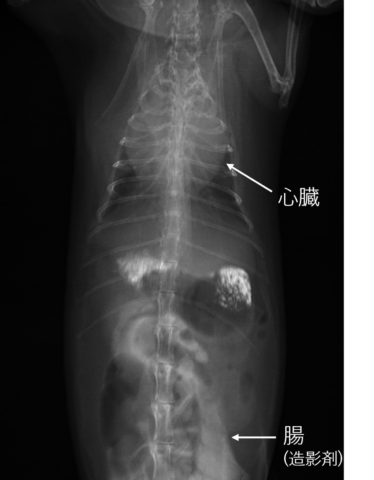

この日、心臓肥大の原因を特定するためのエコー検査を行っていただきました。

心臓に水(心嚢水)が溜まり、加えて肺にも水(胸水)が溜まっているため呼吸が苦しい状態であるとの説明を受けました

心嚢水は抜くことで呼吸が楽になるので、犬だと手術も行えるそうですが、うさぎの心嚢水が溜まるのは珍しいケースな上、オペのリスクが高く、外科的な処置はできないためICUで酸素吸入してから内科療法をメインに治療をすすめるという説明をうけました。

検査の結果、心嚢水のため大きくふくれていた心臓が小さくなり肺に溜まった胸水もなくなっているとのこと